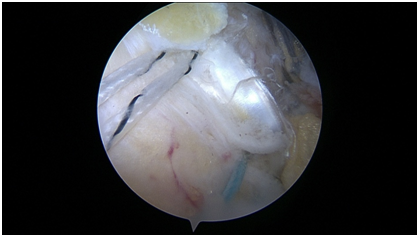

Anchor Bounded hybrid Repair (Figure 4): This technique prioritizes anchors as the primary means of fixation, and allows for the repair of any sized cuff tear with a transosseous equivalent four anchor construct. This repair is typically applied in severely retracted tears, reconstructions, or tears with noncompliant tissue. Anchors are placed at the margins of the tear, securing the mechanically important cables of the rotator cuff, while the intervening tissue is circumferentially opposed to bone with either one or two transosseous tunnels. The tunnels between the anchors respect the biology and bone stock of the tuberosity, while adding additional circumferential compression points of the tendon footprint. Additional tunnels may be created as needed for “dog ears” or further cuff reduction. This paradigm may also be used in superior capsular or graft augmentations, as there are often edges of the graft which must be secured for stability of the graft interface, even after multiple anchors have been used (Figure 5).

Figure 4  Anchor bounded hybrid repair.